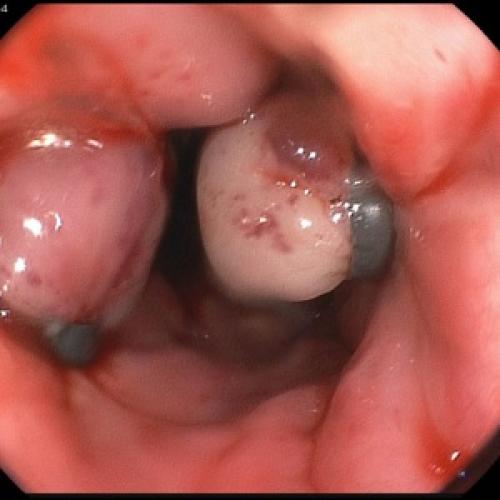

Кишечные кровотечения у пациентов с ХП являются патогномоничным симптомом ложной аневризмы (ЛА) ветвей чревного ствола и верхней брыжеечной артерии . При этом при гастродуоденоскопии не обнаруживают изъязвлений в желудке и двенадцатиперстной кишке, флебэктазий пищевода. Выделение крови из большого сосочка ДПК при дуоденоскопии регистрируется в 14% наблюдений (52).